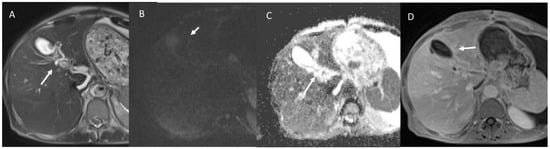

- Granata, V.; Fusco, R.M.; Catalano, O.; Filice, S.; Avallone, A.; Piccirillo, M.; Leongito, M.; Palaia, R.; Grassi, R.; Izzo, F.; et al. Uncommon neoplasms of the biliary tract: Radiological findings. Br. J. Radiol. 2017, 90, 20160561. [Google Scholar] [CrossRef] [PubMed]